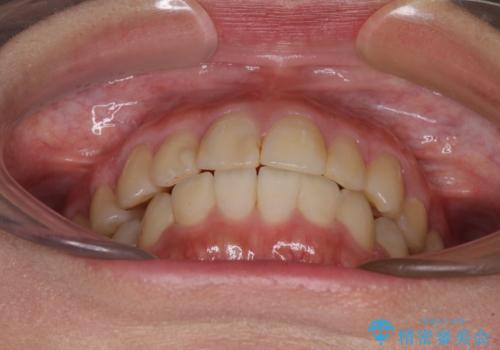

治療期間はかかりましたが、正中も合い、綺麗な仕上がりとなりました。